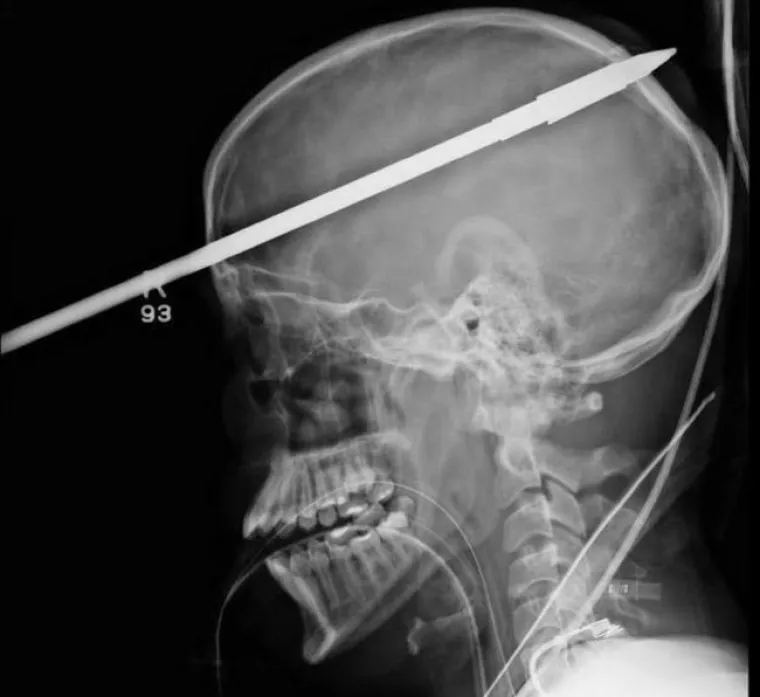

BOLJET ĆE VAS OD SAMOG POGLEDA... Rengenske snimke od kojih će vas proći trnci

Ovaj 16-godišnjak bio je preblizu dok je njegov prijatelj nespretno punio osti